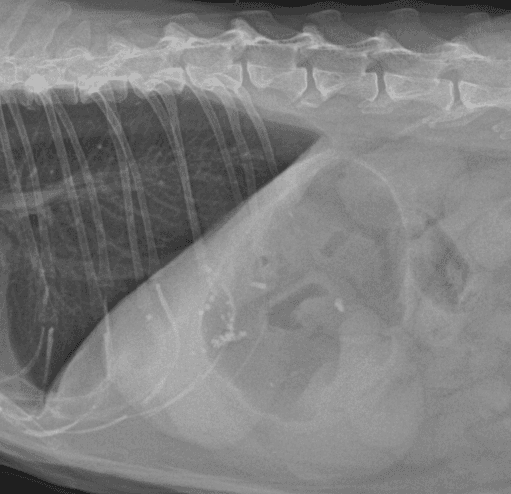

간, 담도 수술은 수술뿐만 아니라, 수술 후 중환자 관리도 중요하기 때문에 외과와 내과의 협진이 매우 중요합니다. 동탄시티동물의료센터에서는 최신 수술 장비의 도입으로 간담도 수술에서 출혈 및 부작용을 최소화 하였으며, 수술 후 협진 시스템을 통해 수술 후 관리에도 최선을 다하고 있습니다.

담석

담낭점액종